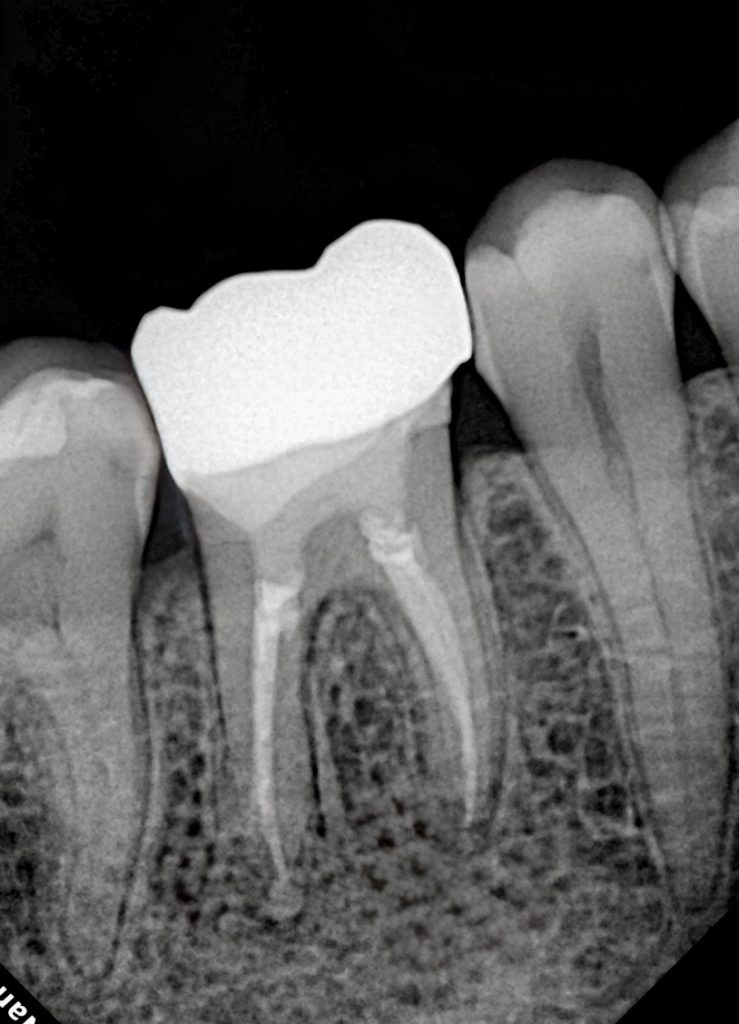

- Canals obturated using warm vertical compaction and bioceramic sealer to optimise apical seal.

- Immediate coronal seal placed post-obturation to prevent reinfection.

- Radiographic healing observed – periapical lesion resolved.

- Surrounding bone density improved.

- Soft tissue response healthy and stable.

- Patient asymptomatic, full function restored.

- Restoration clinically intact with excellent marginal integrity.